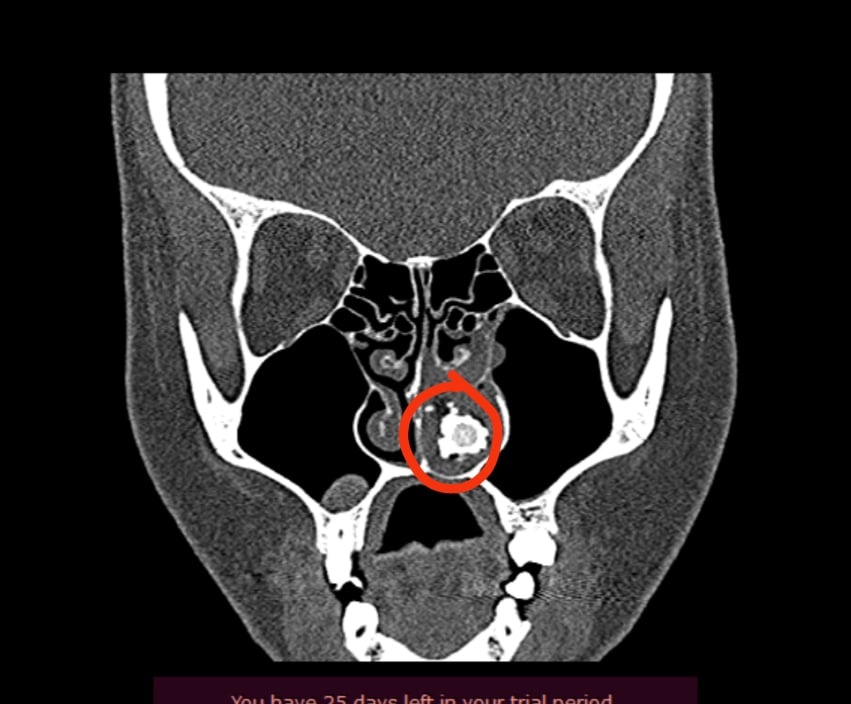

Нижегородские врачи достанут кусок ваты из носа пациента. Инородное тело находилось там не менее десяти лет, рассказал лор-хирург Григорий Белозеров на своей странице во «ВКонтакте».

«Не ковыряйте ватной палочкой в носу. Одно неловкое движение — и ватный кончик попадает глубоко в полость носа», — написал врач.

По его словам, со временем вата превращается в камень — ринолит и провоцирует воспаления. Удалять вату будут хирургическим путем.